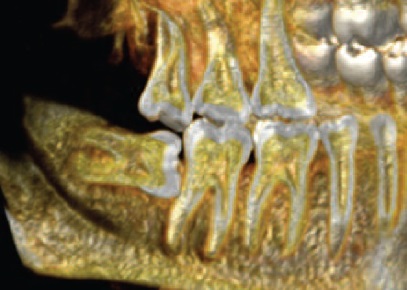

Наиболее часто альвеолит возникает после удаления зубов нижней челюсти, особенно третьих моляров с затрудненным прорезыванием, при котором происходит значительная травма мягких тканей и кости челюсти. Так, на рис. 3 и 4 представлены клинические случаи затрудненного прорезывания аномально расположенных зубов 48. Особенности расположения зуба 48 и его соотношения с зубом 47 позволяют предположить с высокой долей уверенности, что удаление зуба 48 будет очень травматичным.

Рис. 4. Аномалия положения зуба 48.